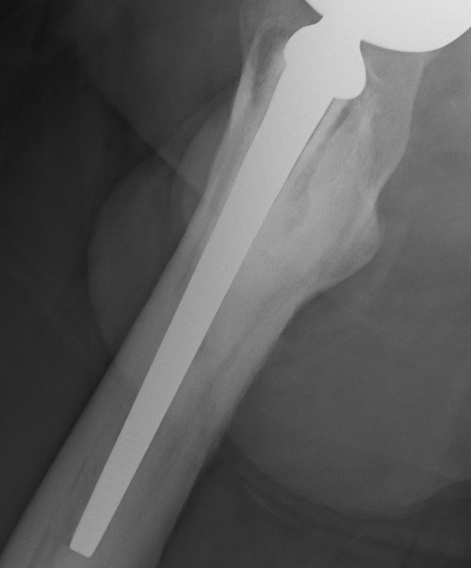

We reviewed my X-rays and confirmed the osteolysis and bone loss. The health of the bone at the top of the femur is a concern and I am going to have a nuclear medicine bone scan tomorrow morning to see what is going on with the blood flow to and around the bone.

The movement of the prosthesis, or lines suggesting movement within the femur where obvious (it seems?).

And then he will need to dig out the femoral implant but the way it looks that should come out very easily – but he will then have to dig out the old cement and the cement that spewed down the femur when the last surgeon did not use a glue cup.

A longer femoral stem will be required and he may get away with a press fit – time will tell.